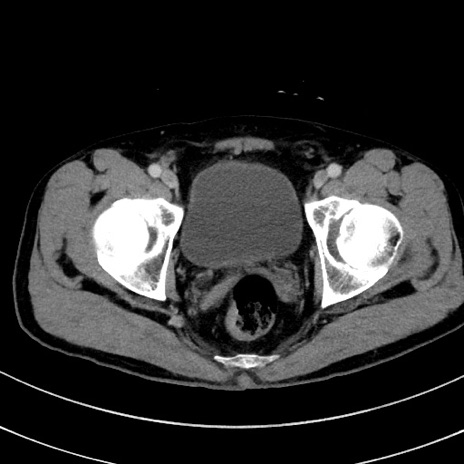

症例8(横断像)

【症例】 60歳代男性

【主訴】 黒色吐物

【現病歴】 4日前から嘔気自覚、2日前の朝食後にも嘔気あり、自分で手で嘔吐反射起こし嘔吐したところ血が混ざっていたため受診。

【既往歴】 5年前汎発性腹膜炎を伴う急性虫垂炎で手術、高血圧、前立腺肥大症、高脂血症

【身体所見】 腹部正中に手術癩痕あり 腹部平坦・軟圧痛なし膨満感あり

【データ】WBC 8400、CRP 4.54